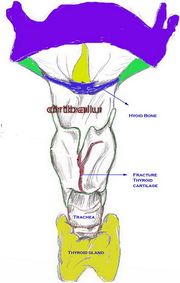

| 12:14, 22 October 2018 | Fract larynx.jpg (file) |  |

60 KB | Drtbalu | |